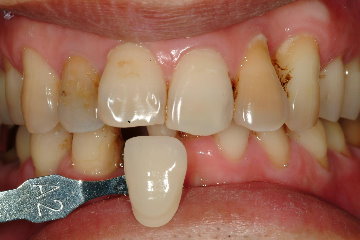

經過四週後,由於傷口癒合良好,準備製作假牙,由於是前牙區,因此顏色相當重要,因此使用數位比色(圖七)及數位攝影(圖八),取得牙齒之精確顏色分佈。

圖八 |